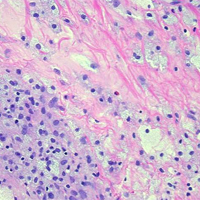

Richard J. Grostern, MD is fellowship trained in ocular pathology and oversee the department's clinical and educational pathology program. The resident laboratory experience takes place during the first year. Each first-year resident participates in two three-month rotations on the ophthalmic pathology service. Residents evaluate gross specimens and prepare them for fixation. Additionally, there are formalized one-on-one teaching with Dr. Grostern in the pathology lab. Although the volume of specimens derived from Rush patients is sufficient for the educational experience, additional unknown cases from the Ocular Pathology Library fortify the rotation. Dr. Grostern serve as ocular pathologist for the Cook County Medical Examiner. Emergency specimens can be processed and reviewed on virtually any day by the team. There is a one-hour block each month to conduct a pathology conference with the residents in morning didactic conferences.